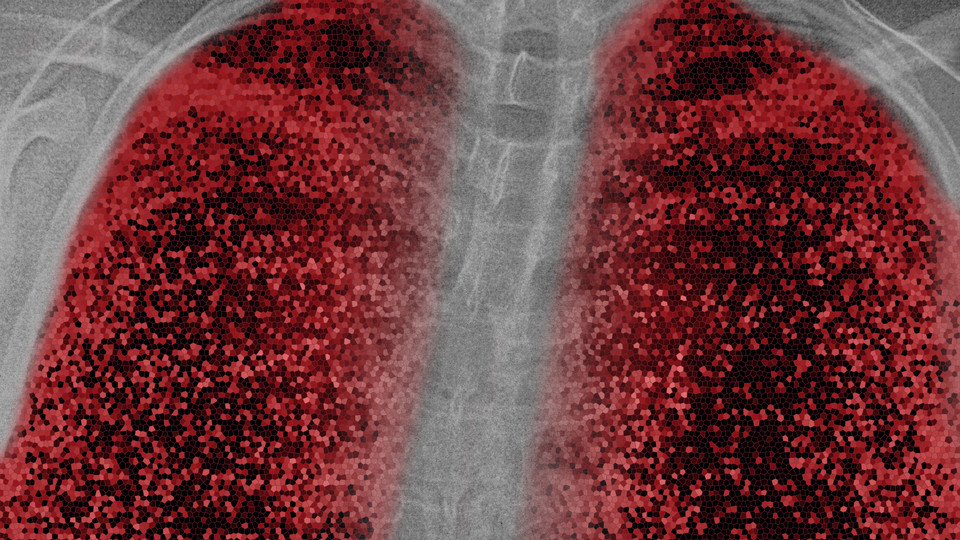

Yeni tip koronavirüs (Covid-19) ile enfekte olan hastaların 3 ay sonra yeni bir tarama yöntemiyle incelenen akciğerlerinde hasar tespit edildi. Oxford Üniversitesinden bilim insanları, yaşları 19 ila 69 olan 10 hastanın akciğerlerini ksenon gazı kullanarak manyetik rezonans (MR) ile taradı.

AA'nın BBC kaynaklı haberine göre, tarama sırasında ksenon gazını içine çeken hastalardan nefes darlığı çektiğini söyleyen 8'inde, akciğer hasarının işaretleri görüldü.

HASAR GELENEKSEL TARAMA YÖNTEMLERİYLE TESPİT EDİLEMİYOR

Uzmanlar, hastalardaki akciğer hasarının, geleneksel tarama yöntemleriyle tespit edilemediğine de işaret etti.